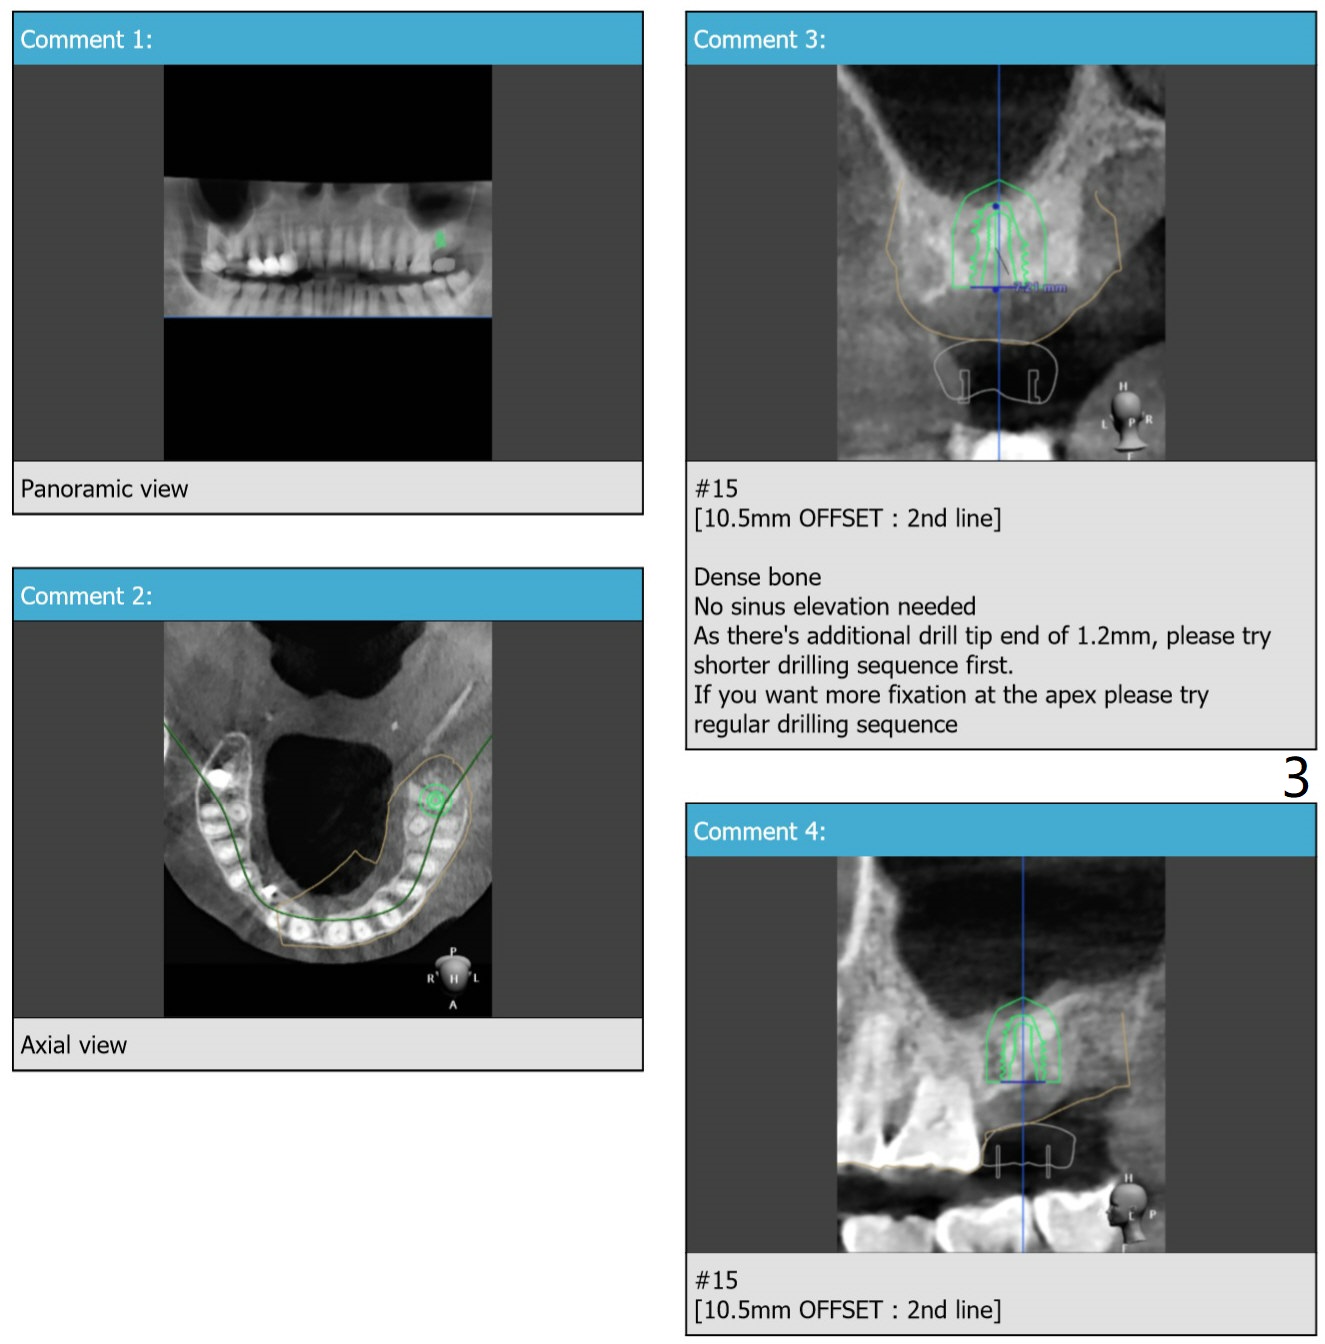

No Sinus Lift

Return to No Deviation

Xin Wei, DDS, PhD, MS 1st edition 01/29/2020, last revision 04/14/2020